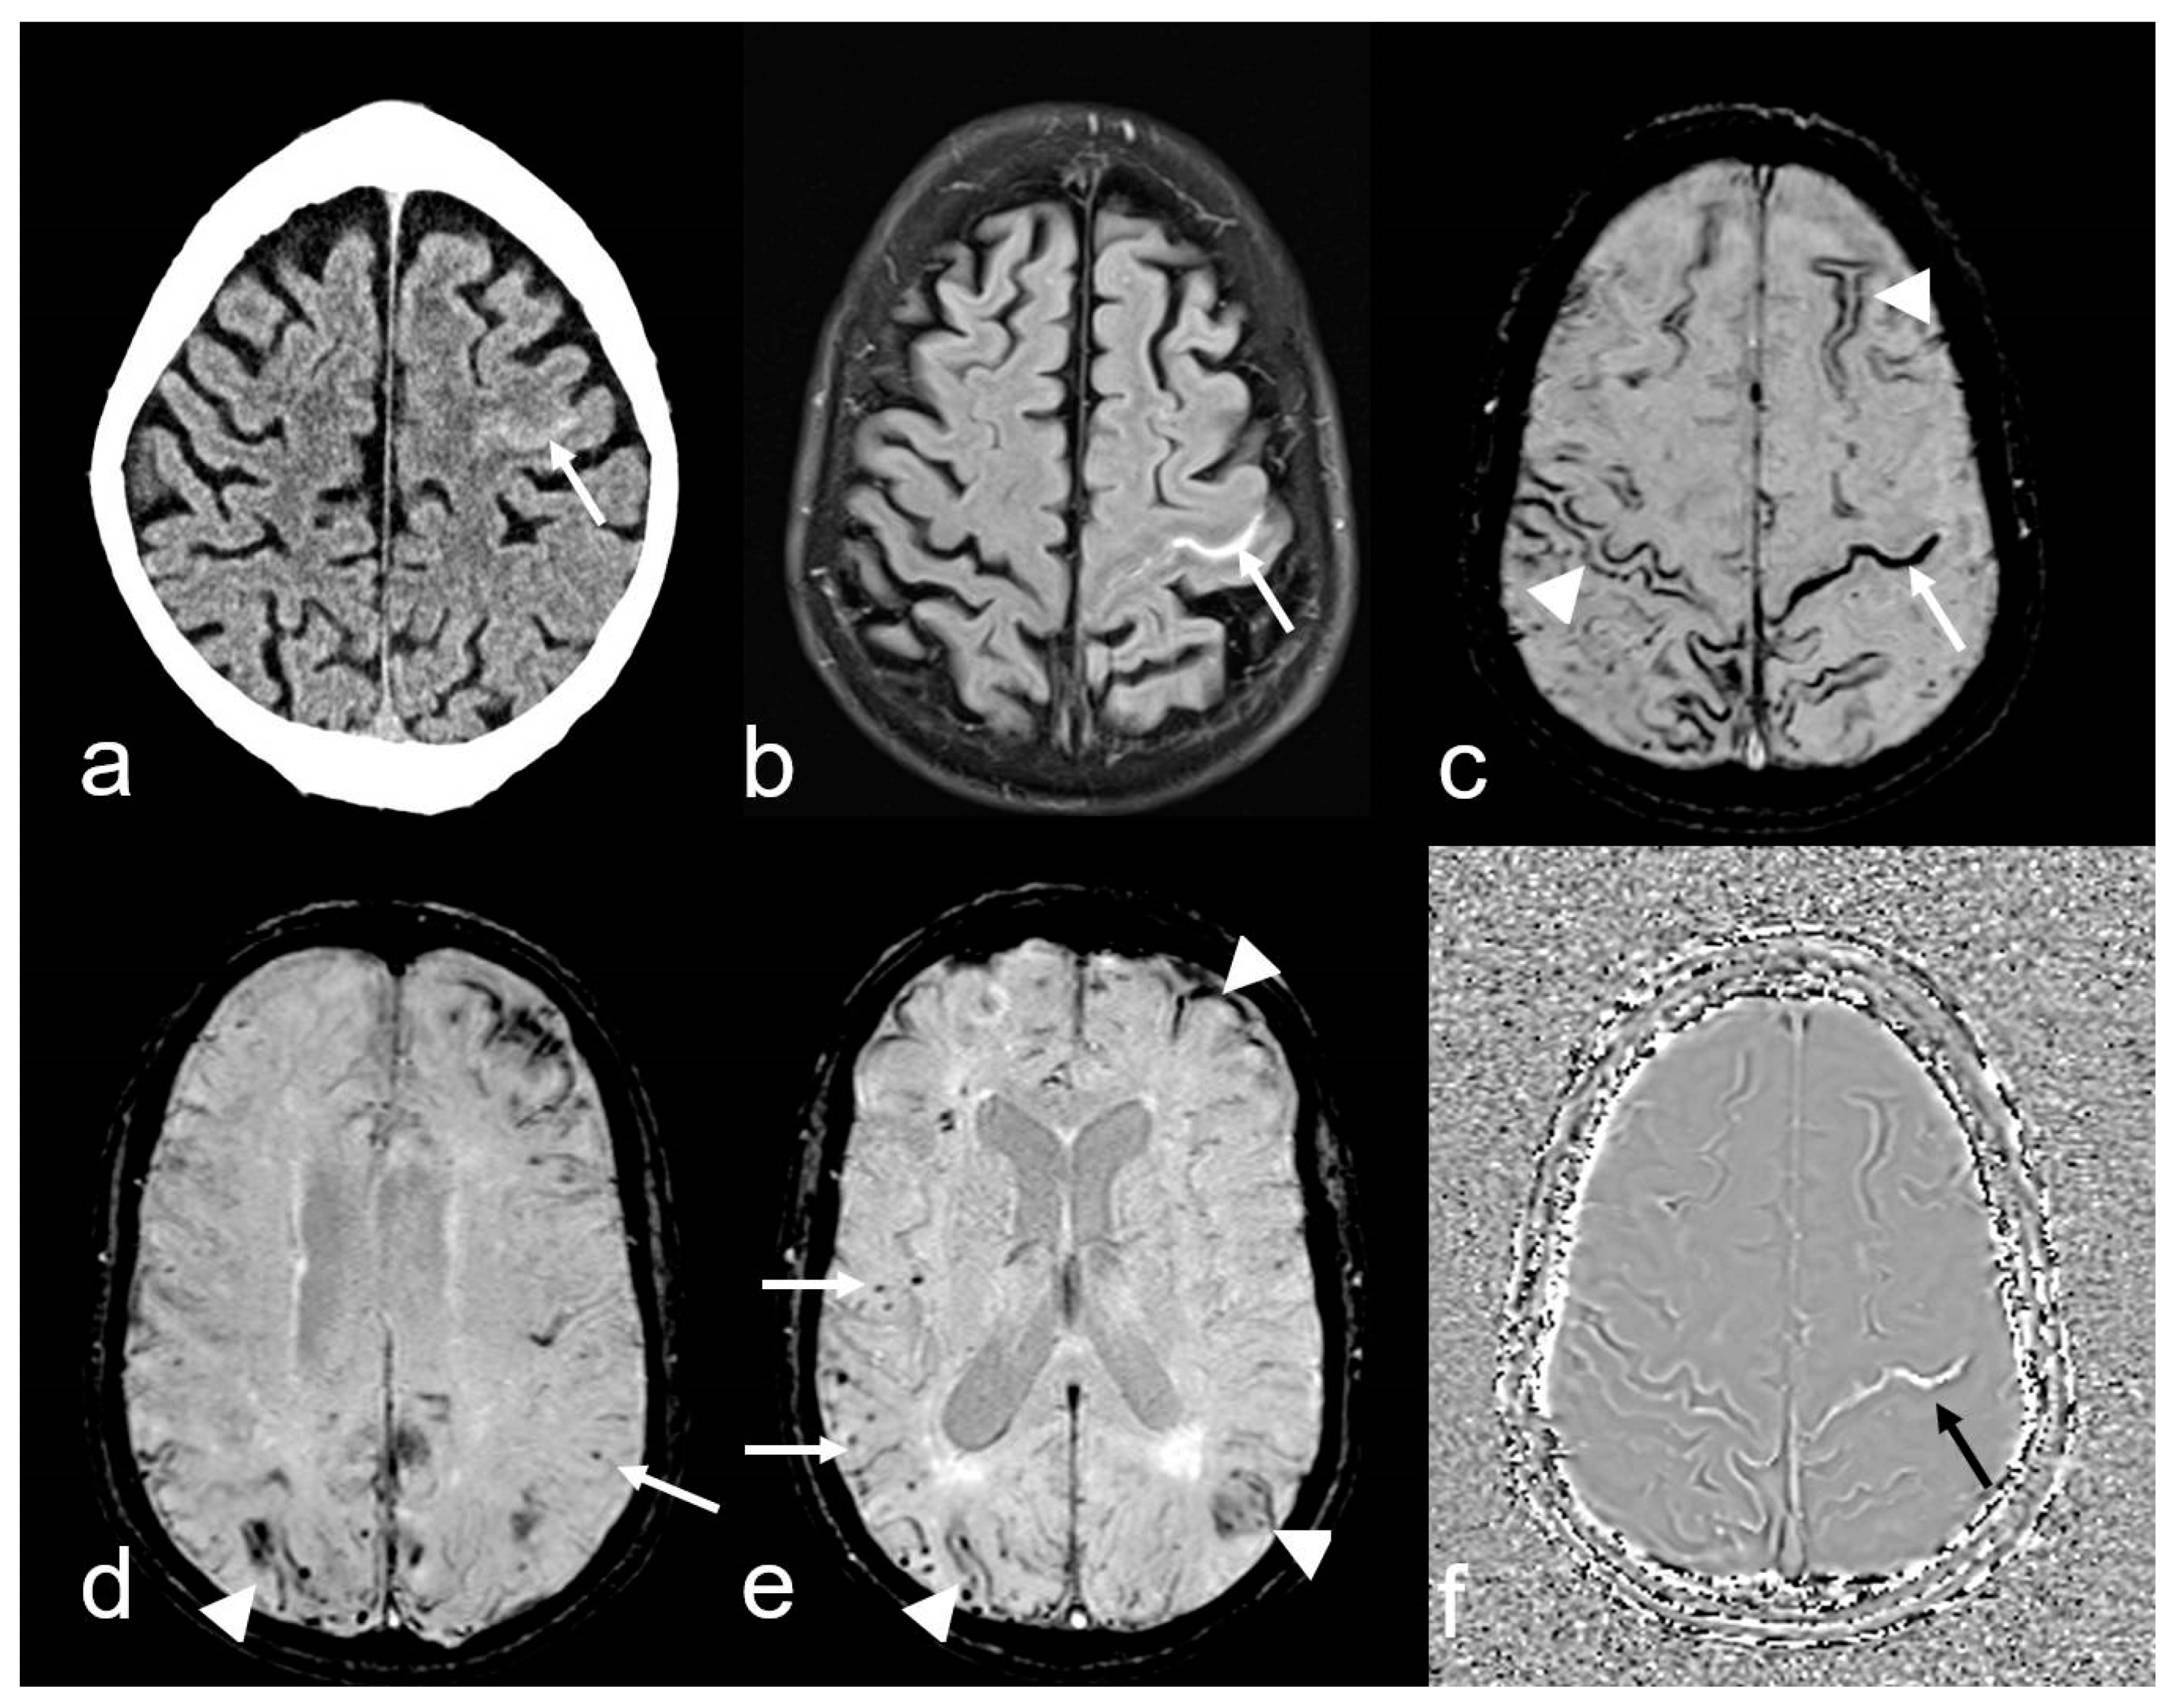

Figure 4.

A 74-year-old man with progressive cognitive impairment suffering from temporary sensory–motoric deficits right. Cortical subarachnoid hemorrhage (cSAH) in the central sulcus ((a), CT: arrow; Siemens Somatom Emotion). MRI with sulcal hyperintense signal changes on fluid attenuated inversion recovery (FLAIR) images ((b), arrow), sulcal signal loss on susceptibility-weighted imaging (SWI, (c): arrow), additional multifocal cortical superficial siderosis (cSS) bilateral ((c–e), arrowhead); note the characteristic bilinear track-line appearance of cSS in the chronic stage ((c), arrowhead); (d,e): multiple cortical/subcortical microbleeds (MB, arrow); (f): SWI-phase image demonstrating paramagnetic effects in the central sulcus due to blood degeneration products (arrow); MRI 1.5 T Siemens AREA.

4. Cortical superficial siderosis (cSS) refers to the presence of linear hemosiderin in the leptomeninges and the superficial layers of the cerebral cortex, most commonly as a sequela of a previous acute cSAH [62,65,66,67,68,69,70]. It is important to differentiate between localized cSS, which affects 1–3 sulci, and disseminated cSS, which affects at least 4 sulci [70]. In the acute stage, T2*-weighted imaging (WI) and susceptibility-weighted imaging (SWI) typically show homogeneous signal loss, while in the chronic stage, a bilinear, “track-line” appearance is characteristic (Figure 4) [63,65,66].